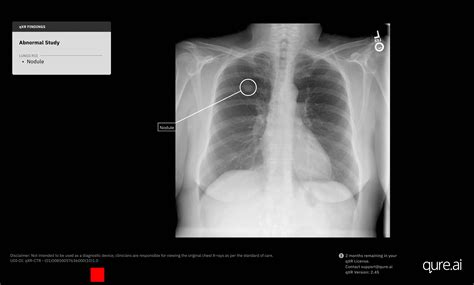

Nodules and Masses

Nodules are small, round opacities, while masses are larger and more irregular. They can be benign or malignant. Common causes include lung cancer, metastases, and infections.